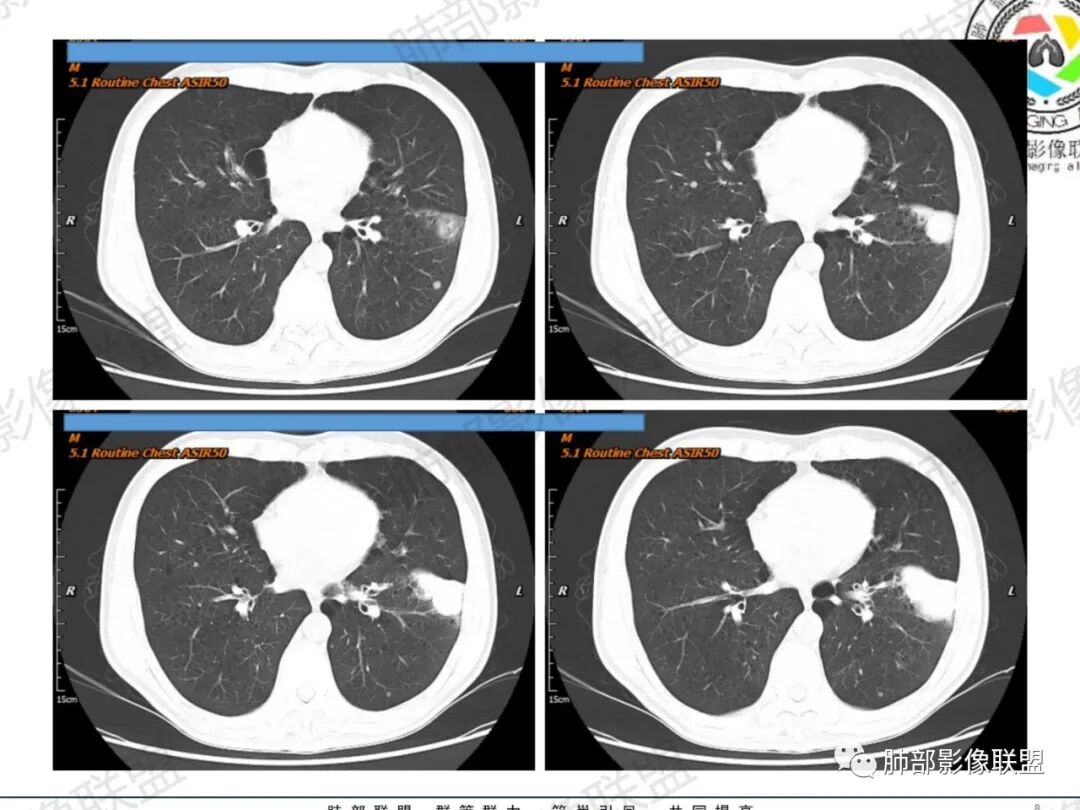

一切∮随缘:左肺下叶不规则肿块,边缘光滑,平直,局部彭隆,分叶,近端支气管堵塞,远端与胸膜相贴,平扫密度尚均匀,增强后不均匀强化,内部可见低密度坏死,胸膜下多发肺气肿,伴双肺散在光滑小结节,实验室肿瘤标志物高,考虑恶性:神经内分泌癌(大细胞),腺癌,鳞癌。

琦遇:恶性没有问题,肺气肿底子、病灶分叶、少许毛刺、叶间胸膜凹陷、部分边缘可见清晰的GGO、胸膜牵拉凹陷、局部胸水、近端支气管截断、部分支气管被推移、占位效应明显、强化特点为不均匀强化、内部有少许沼泽样低强化区,强化部分轻中强化为主、余肺可见转移性结节、左肺上叶似为囊腔型腺癌一枚,肿瘤标志物提示非小、神经内分泌,综合分析考虑大神泌、腺癌、腺鳞癌、鳞癌  同时左肺上叶囊腔型腺癌  肺转移

飞鹰行动:中年人,男性,胸疼入院,左肺下叶占位,张力较高,边界可见分叶,局部可见明显收缩性改变,增强病灶内部有延迟强化表现,考虑恶性病变,大细胞癌伴肺内转移或者囊腔样腺癌伴转移。

蕊:中老年男性,吸烟史,肺气肿背景,左肺上叶类圆形肿块影,边界清晰,边缘凹凸不平,有分叶,支气管进入阻断,临近胸膜栽赃,整体病灶膨隆,局部周围可以清晰ggo,临近叶间裂内凹,轻度强化,并可见多个低密度区,坏死可能,界线不清;肺内多结节,边缘光滑,考虑恶性伴转移,鳞癌、腺癌

傅昌瑜:中老年男性,肺气肿背景,右胸背疼痛1周。CEA、NSE、CYFRA—211升高。左上肺混合磨玻璃结节,内见较多空泡和扩张支气管。左下肺胸膜下肿块,边缘较光滑,深分叶,似有血管进入,与支气管关系不清,内见不均匀强化,见沼泽地样坏死,有胸膜栽赃。另两肺多发圆形小结节。考虑恶性并肺内转移,多原发可能性大,左上肺腺癌,左下肺病理难以判断,小细胞癌?鳞癌?

小锁:中老年男性,肺气肿背景,右胸背疼痛1周。CEA、NSE、CYFRA—211升高。左上肺混合磨玻璃结节,边界清楚,内见较多空泡。左下肺肿块,边缘清楚,深分叶,有血管和支气管进入,胸膜凹陷。另两肺多发圆形小结节。考虑双发原位癌,左上肺腺癌,左下肺大神泌或腺鳞癌可能,肺内转移。

蓝天白云:中年男性,肺气肿背景,左肺下叶肿块,边缘膨隆,有分叶,内有湖泊样坏死,有轻中度强化,局部胸膜栽赃,收缩力不强,周围见肺气肿征象。左肺上叶混合磨玻璃影,边界清楚,考虑都是恶性,左上肺iac,左下肺腺鳞癌,或大细胞肺癌可能。两肺多发结节,考虑转移

毛勤香:老年男性,肺气肿背景,左肺下叶肿块,分叶,边缘光滑,土豆块样,细支气管闭塞,增强轻度不均匀强化,似有坏死,左肺另见多发结节,淋巴结未见明显肿大,恶性确定,吸烟史,鳞癌破坏力强,侵袭力差,多原发的一般很少多于3个,故排后,首先考虑神经内分泌癌,局部血管穿行,鉴别淋巴瘤

周太狼:中年男性,吸烟、高血压史,肿瘤指标升高,肺气肿背景下,左肺下叶肿块影,分叶、膨隆、未跨叶裂,支气管截断,不均匀强化。另双肺多发结节及磨玻璃影,左肺上叶混合磨玻璃,内可见多发空泡影。整体考虑恶性,肺癌伴肺内转移,左下肺鳞癌?神经内分泌癌?左肺上叶囊腔腺癌?